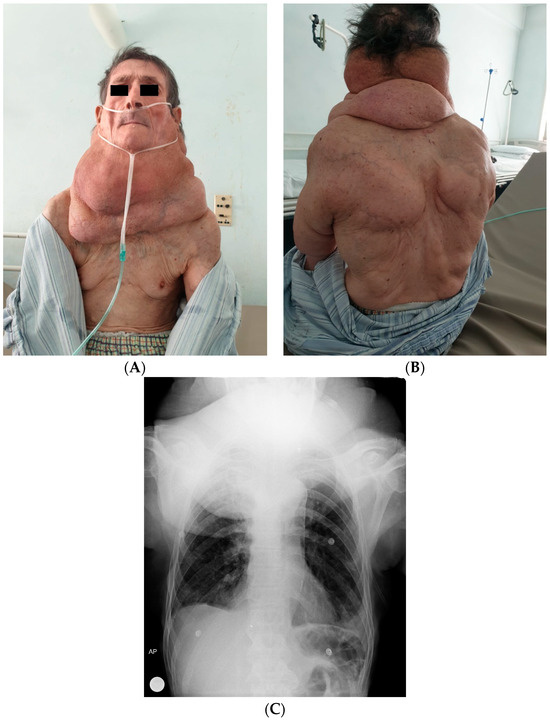

3. Results

4.2. Diagnosis of BSA

4.3. Differential Diagnosis, Comorbidities, and Malignant Transformation in BSA